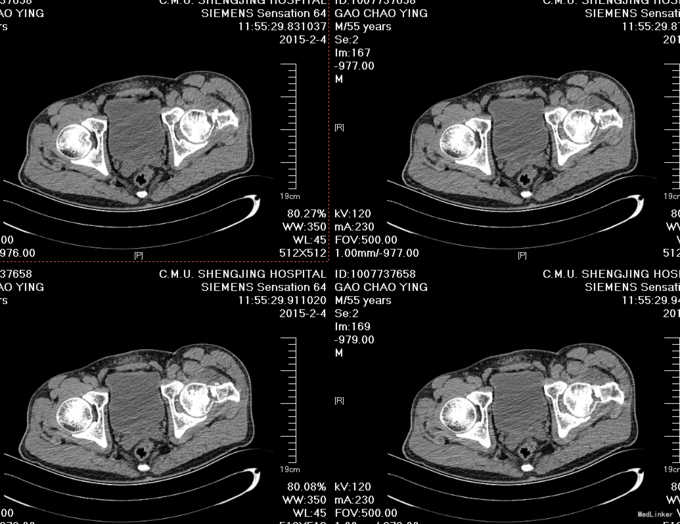

主诉:摔伤后左髋部疼痛活动受限8小时 患者自述于2015-2-3日15时在工厂干活时不慎由梯子上摔落(高约2米),致左髋部疼痛、活动受限,不能站立行走,急送至抚顺市中医院行骨盆DR示:左股骨颈骨折。现患者为求进一步诊治来我院,急诊以“左股骨颈骨折”为诊断收入我科。患者自受伤以来一般状态可,无发热,无头晕、呕吐,无胸闷、心悸呼吸困难,无腹痛、腹泻,饮食可,睡眠可,二便正常。

患者入院后完善相关检查,查无明显手术禁忌症后行左股骨颈骨折闭合复位空心钉内固定术。患者术后卧床休息,给予接骨等对症治疗。